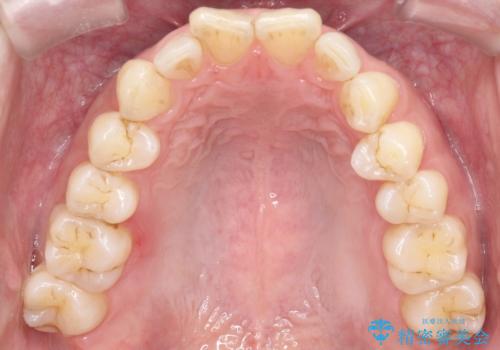

【インザライン】前歯の凸凹を治したい

- 前歯の凸凹を主訴に来院されました。

下顎位が右方に変異しており、外科矯正も提案しましたが患者様は希望されず、インビザラインにて治療を完了しております。

叢生のスペースを確保するために、臼歯部の遠心移動を行っています。

今回の治療計画は上顎の正中を顔と揃えることを優先しています。